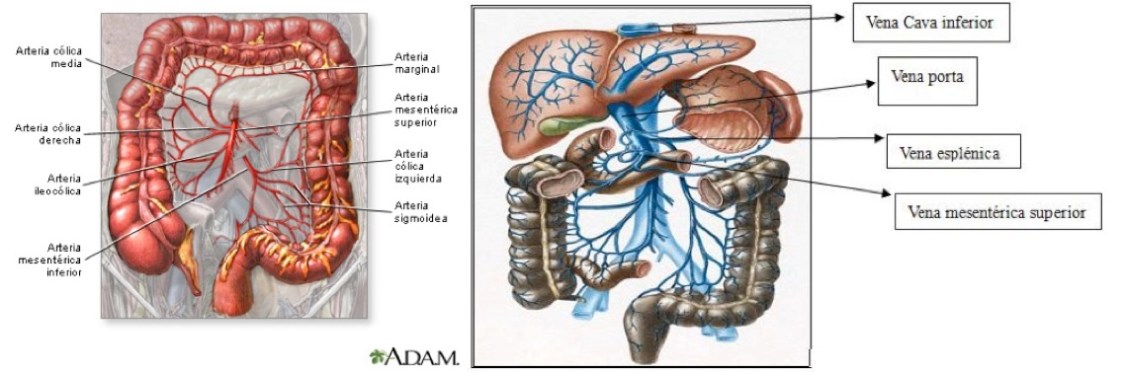

El intestino delgado y grueso está vascularizado por tres arterias que irrigan diferentes regiones:

1º- Tronco celiaco: vasculariza desde el esófago distal hasta la 2ª porción duodenal o duodeno descendente. Se compone de:

- Arteria gástrica izquierda.

- Arteria hepática común (se divide luego en gastroduodenal y hepática propia).

- Arteria esplénica.

2º- Arteria mesentérica superior (AMS): desde 3ª porcion duodenal hasta el colon transverso y flexura esplénica. Mencionar que la arteria gastroduodenal (primera rama de la hepática común) forma una importante conexión con la AMS.

La AMS forma otras importantes anastomosis con la AMI: arteria marginal de Drummond y la arcada de Riolano.

3º- Arteria mesentérica inferior (AMI): desde la flexura esplénica del colon hasta el recto. Forma además conexiones con las ramas lumbares, las arterias sacras e iliacas internas.

Las venas mesentéricas superior (VMS) e inferior (VMI) discurren paralelas a sus arterias y drenan la sangren de los diferrentes territorios subsidarios. La VMI se vacía en la vena esplénica, la cual se une a la VMS para formar la vena porta. En su discurrir, las venas mesentéricas forman anastomosis y colaterales con otras venas desde las gástricas y esofágica hasta renales, lumbares y pélvicas.